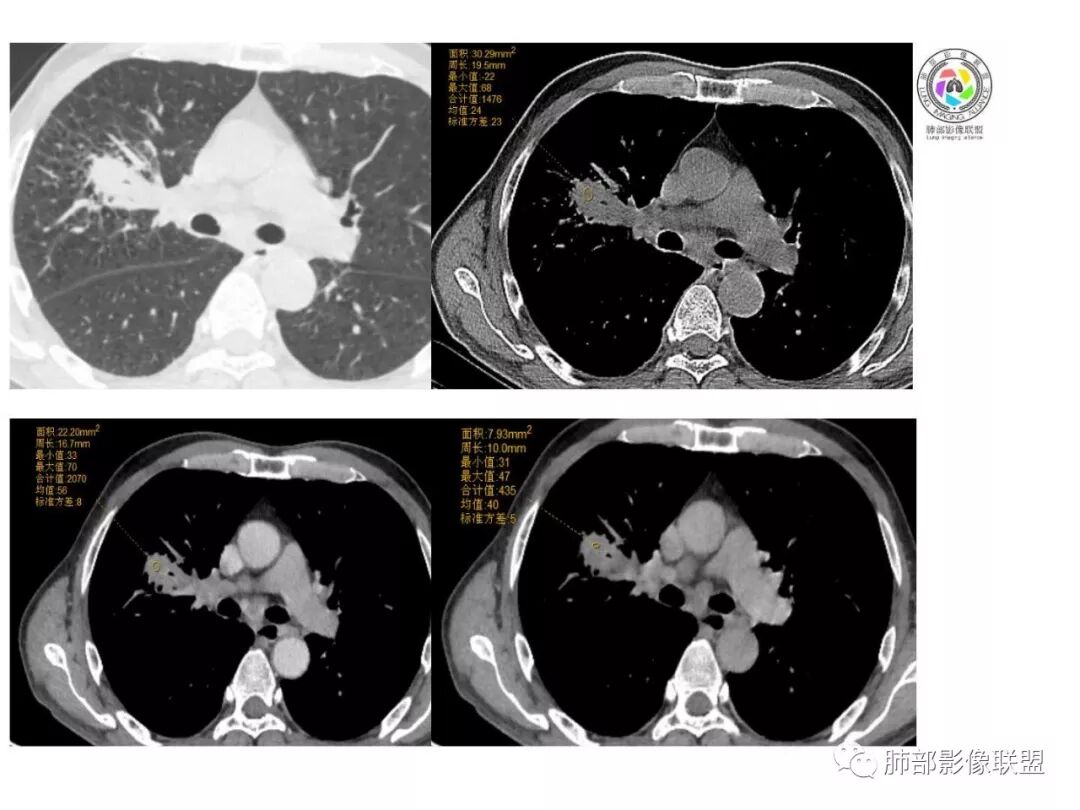

右肺巨大肿块,跨叶生长,其内见大片状坏死,坏死边界不清,血管进入,边缘受侵,病灶边缘可见毛刺及分叶,病灶强化方式速升速降,纵隔内见坏死强化淋巴结,周围肺叶小叶间隔结节样增厚,考虑恶性腺癌并淋巴结转移及癌性淋巴管炎,鉴别肉瘤。

右肺中叶可见类圆形软组织密度肿块影,右肺中叶外侧段支气管狭窄截断。肿块密度不均,边缘毛燥不规则,可见毛刺。远侧肺内可见网格条索影。增强后可见不均匀强化。纵隔淋巴结肿大,部分融合。考虑右肺恶性病变,鳞癌>腺癌,并纵隔淋巴结转移。

患者中老年男性,体检发现肺部占位。

胸CT:右肺中叶实性占位性病变,呈膨胀性生长,对斜裂明显挤压,右肺中叶外侧段阻塞,并在边缘可见分叶、毛刺、棘突样改变,胸膜牵拉;增强可见病灶明显强化,可见边缘模糊血管影,病灶内可见大片状低密度区,隆突下可见肿大淋巴结。

诊断考虑:恶性病变。

患者中老年男性,体检发现右肺占位。血常规轻度贫血,AFP、CEA正常,肝肾功能、血糖、血脂、心肌酶、电解质正常。胸部CT:右肺中叶巨大肿块灶,垮叶生长,可见分叶、毛刺、血管集束、支气管截断征象,远端周围可见小叶间隔增厚,增强轻度强化,内可见低密度坏死区,综合淋巴结肿大,且可见淋巴结内似低密度灶。综合考虑恶性,鳞癌并癌性淋巴管炎可能大。鉴别结核、腺癌。

胸CT:右肺中叶团块样实性占位,边缘膨隆,中叶外侧段阻塞,病灶可见深分叶、棘突,胸膜牵拉;增强不均匀强化,可见边缘模糊血管影,病灶内大片状低密度区,纵隔多发肿大淋巴结。

诊断考虑:恶性病变,鳞?大细胞?鉴别:TB